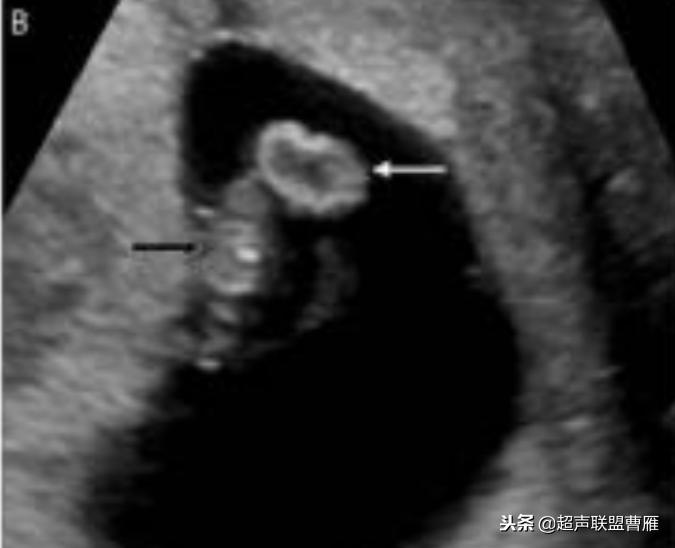

卵黄囊钙化

钙化卵黄囊6.6mm,一周后胚胎死亡

· 卵黄囊不规则或钙化:出现囊壁钙化或者增厚等形态改变以及囊壁缺损,提示 卵黄囊功能衰退与营养障碍,预示妊娠结局不良。一般情况下,出现钙化通常胚胎已停育。